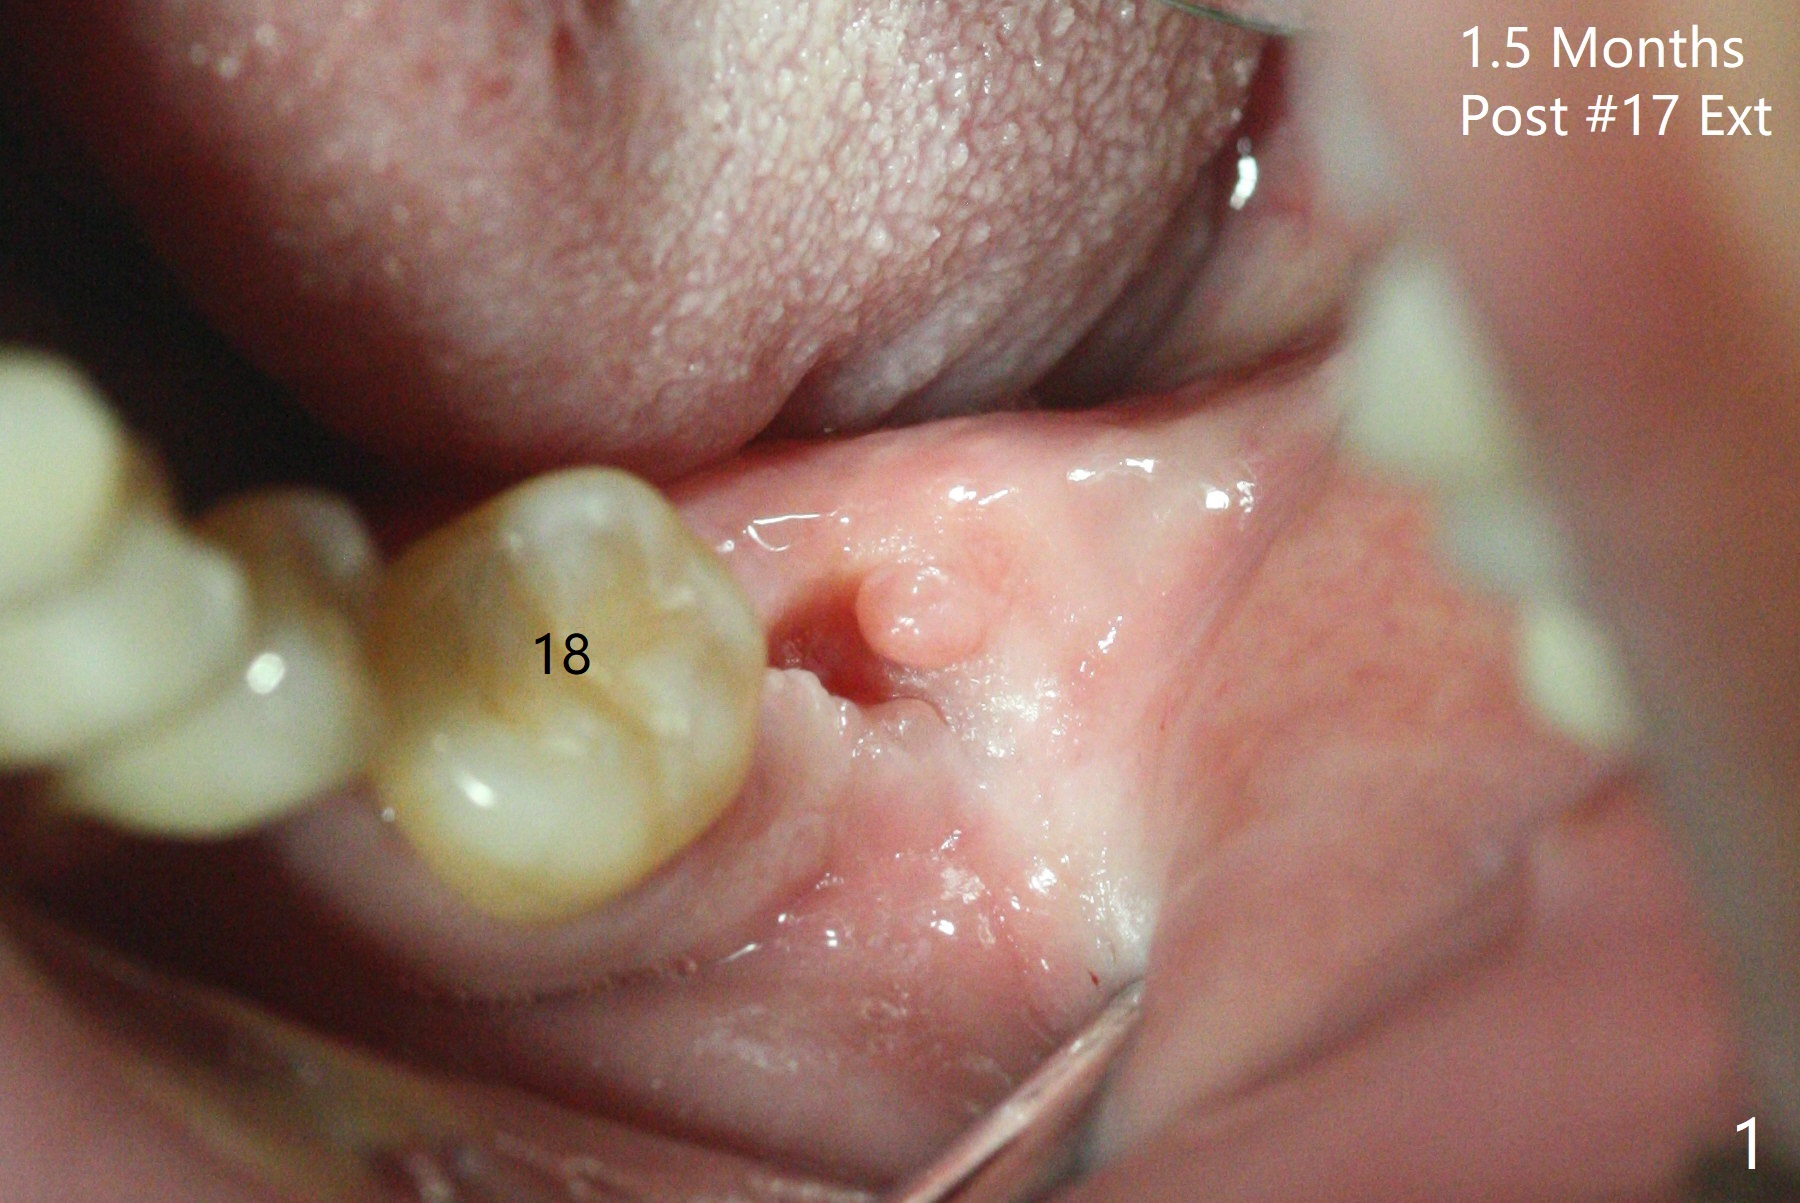

#17牙拔除植骨后1.5月(图一),准备在牙槽窝远中,即升支,种植一个抛锚,局麻下,首先不切开,钻洞,有些不放心,后来切开植入2x10(2)毫米一段式带球状基台植体(图二),植体根尖好像进入神经管(N)。CT显示植体却植入太接近舌侧骨板(图三:L),其实应该术前拍摄CT。由于18号牙同时扭转,安置磨牙圈(molar band),利用power chain进行牵拉以及矫正扭转(图四)。问题:升支抛锚种植位置对吗?power chain挂在抛锚上不稳定。